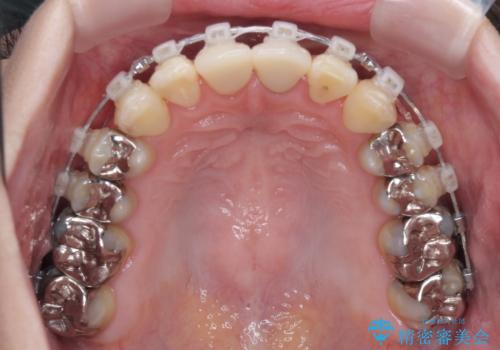

- クリアブラケット

ワイヤー装置、マウスピース、どちらの装置でも治療は可能でしたが、マウスピース矯正の自己管理の煩わしさを懸念され、ワイヤー装置にて矯正治療を行うこととしました。

前歯の黒い縁は、矯正治療後にオールセラミッククラウンにて改善することとしましたが、いち早く目立たなくしたいとのことで、事前に矯正治療用仮歯に置き換えてから矯正治療を開始しました。

前歯を早々に仮歯に置き換えたことで、矯正治療に意欲的に臨んでくださいました。